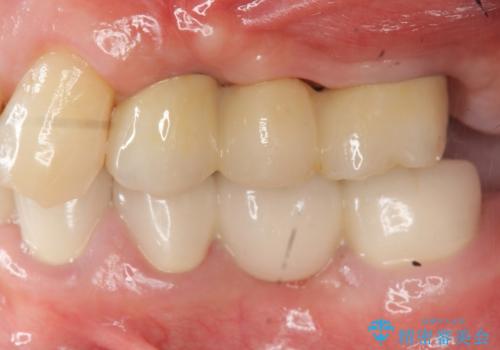

しっかりと造骨を行ったことでインプラント周囲には十分な量の骨が存在し安定したインプラント周囲環境を整えることができました。

最終的なジルコニアクラウン装着後は、まるで自分の歯のように咬める、と咬合機能の回復を大変喜んでいただくことができました。